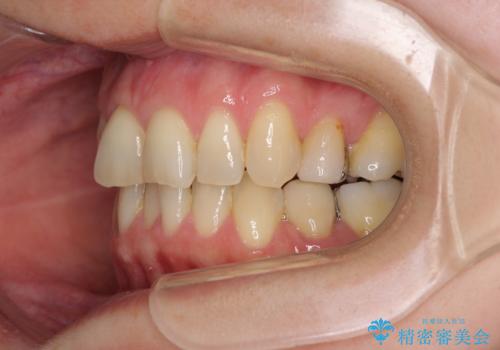

矯正の後戻りの改善と銀歯をセラミックに

- 上下前歯の叢生を気にして来院された患者様です。

費用を抑え、期間もあまりかけずに治療をしたいとのことで、インビザライン・ライトを用いて矯正治療を行うこととしました。

矯正治療後には、下顎臼歯の目立つ銀歯をセラミックインレーにて修復治療を行いました。

軽微な後戻りの治療であったため、十分に治療を行うことができました。

口を開けたときに金属が見えなくなり、患者様には大変満足していただきました。